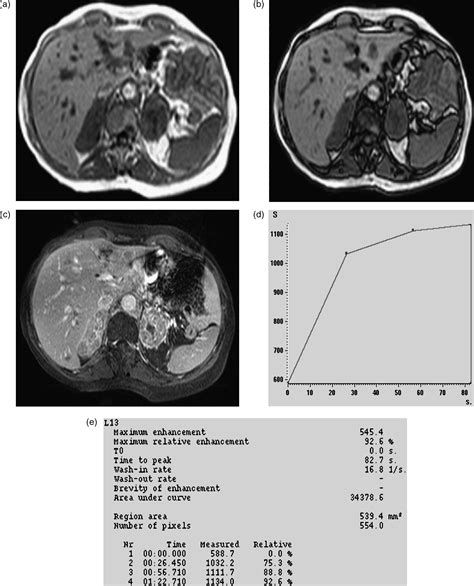

• Imaging tests: Computed tomography (CT) scans and magnetic resonance imaging (MRI) are commonly used to detect adrenal adenomas. These tests provide detailed images of the adrenal glands and can help determine the size and location of the tumor.